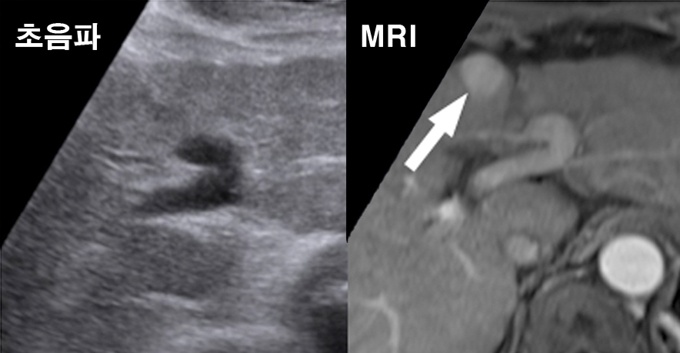

°£°æÈ­ ȯÀÚ¿¡°Ô ÃÊÀ½ÆÄ°¡ ¾Æ´Ñ MRI·Î ÁÖ±âÀûÀÎ °Ë»ç¸¦ ½Ç½ÃÇÒ °æ¿ì °£¾Ï Á¶±â ¹ß°ßÀ²ÀÌ ÃÖ´ë 3¹è ³ôÀº °ÍÀ¸·Î ³ªÅ¸³µ´Ù.

¼­¿ï¾Æ»êº´¿ø ¼ÒÈ­±â³»°ú·¿µ»óÀÇÇаú °øµ¿ ¿¬±¸ÆÀÀº °£°æÈ­ ȯÀÚµéÀ» ´ë»óÀ¸·Î MRI¿Í ÃÊÀ½ÆÄ °Ë»ç¸¦ 6°³¿ù °£°ÝÀ¸·Î ½Ç½ÃÇÑ °á°ú, °£¾Ï Á¶±â ¹ß°ßÀ²ÀÌ °¢°¢ 86%¿Í 27.9%·Î ³ªÅ¸³µ´Ù°í 18ÀÏ ¹àÇû´Ù.

ÇöÀç ±¹Á¦ Áø·áÁöħÀº °£¾Ï ¹ß»ý °¡´É¼ºÀÌ ³ôÀº °£°æÈ­ ȯÀڵ鿡 ´ëÇØ 6°³¿ù¸¶´Ù ÃÊÀ½ÆÄ °Ë»ç¸¦ ¹Þµµ·Ï ±Ç°íÇϰí ÀÖ´Ù.

1Â÷ °Ë»ç¿¡¼­ MRI´Â 27¸í, ÃÊÀ½ÆÄ´Â 11¸í¿¡°Ô¼­ ¾Ï¼¼Æ÷¸¦ ¹ß°ßÇß´Ù. 2Â÷ °Ë»ç¿¡¼­´Â MRI·Î 8¸í, ÃÊÀ½ÆÄ·Î 1¸íÀ» °£¾ÏÀ¸·Î Áø´ÜÇß°í, 3Â÷ ¶§¿¡´Â MRI¸¸ °£¾ÏȯÀÚ 2¸íÀ» Ãß°¡ÀûÀ¸·Î ã¾Æ³Â´Ù.

¿¬±¸±â°£ µ¿¾È ÃÑ 43¸íÀÌ ½ÇÁ¦ °£¾ÏÀ¸·Î ÆÇÁ¤µÅ, MRI´Â 86%(37¸í)ÀÇ °£¾Ï ¹ß°ßÀ²À» º¸ÀÎ ¹Ý¸é ÃÊÀ½ÆÄ °Ë»ç´Â 27.9%(12¸í)¸¦ ±â·ÏÇß´Ù.

ƯÈ÷ 2Â÷‧3Â÷ °Ë»ç±â°£ µ¿¾È MRI´Â ȯÀÚ 10¸í¿¡¼­ °£¾ÏÀ» ¹ß°ßÇßÁö¸¸ ÃÊÀ½ÆÄ´Â ´Ü 1¸í¿¡ ±×ÃÆ´Ù.

¶ÇÇÑ Á¾¾ç Å©±â°¡ 2cmº¸´Ù ÀÛ¾Æ ¿ÏÄ¡Àû Ä¡·á°¡ °¡´ÉÇÑ °£¾Ï ±ØÃʱ⠴ܰè(0±â)ÀÎ °ÍÀ¸·Î ³ªÅ¸³­ ȯÀÚ(32¸í)ÀÇ 84.8%°¡ MRI °Ë»ç·Î ¹ß°ßµÆ´Ù.

¾Æ¿ï·¯ ½ÇÁ¦ °£¾ÏÀÌ ¾ø´Âµ¥ °£¾ÏÀÌ ÀÖ´Â °ÍÀ¸·Î À߸ø ÆÇÁ¤ÇÏ´Â ºñÀ²ÀÎ À§¾ç¼º·üµµ MRI(3.0%)°¡ ÃÊÀ½ÆÄ(5.6%)º¸´Ù 2¹èÁ¤µµ ³·¾Æ °Ë»ç Á¤È®µµ ¿ª½Ã ³ôÀº °ÍÀ¸·Î È®ÀεƴÙ.

ÀÓ¿µ¼® ±³¼ö´Â "ÃÊÀ½ÆÄ °Ë»ç´Â Åõ°ú Á¤µµ Â÷À̸¸À¸·Î ¾ÏÀ» ã¾Æ³»±â ¶§¹®¿¡ È­¸éÀÌ ¸¶Ä¡ Èæ¹é»çÁø°ú °°¾Æ °£°æÈ­°¡ ½ÉÇÑ °æ¿ì¿¡´Â ã±â ÈûµéÁö¸¸ MRI´Â Á¾¾çÀÇ Ç÷°ü ºÐÆ÷¿Í ¼¼Æ÷ ºÐÈ­µµ±îÁö ÇÔ²² °üÂûÇÒ ¼ö ÀÖ´Ù"°í ¸»Çß´Ù.